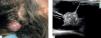

Case ReportA 57-year-old female patient from São Paulo, with a previous diagnosis of metastatic liposarcoma to the liver, was referred to our dermatology center reporting the appearance of a nodule on the right side of the scalp 1 month prior to the consultation, with local radiating pain towards the ipsilateral ear and face. On clinical examination, the scalp topography revealed a firm elevated nodular lesion of smooth surface in the right parietal region, measuring approximately 4.0cm. The skin was flexible and clear without phlogistic signs (Figure 1A). Ultrasound examination (USG) revealed a heterogeneous, well-delimited solid and cystic lesion with hyper-echoic areas, measuring 38 x 33 x 34mm (Figure 1B). Skull tomography showed that bone structures were not affected by the lesion. Differential diagnostic hypothesis included lipoma and liposarcoma metastasis, detected radiologically.

Clinical and imaging characteristics. A) Clinical examination evidencing a nodular lesion on the scalp, with a smooth surface and flexible skin, without abnormalities or phlogistic signs. B) Ultrasonography showing a cystic lesion with a heterogeneous solid area, in addition to hyperechoic areas